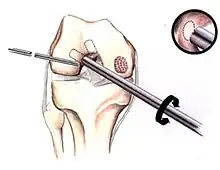

If non-surgical measures are unsuccessful, drilling may be considered to stimulate healing of the subchondral bone. Arthroscopic drilling may be performed by using an antegrade (from the front) approach from the joint space through the articular cartilage, or by using a retrograde (from behind) approach through the bone outside of the joint to avoid penetration of the articular cartilage. This has proven successful with positive results at one-year follow-up with antegrade drilling in nine out of eleven teenagers with the juvenile form of OCD,[53] and in 18 of 20 skeletally immature people (follow-up of five years) who had failed prior conservative programs.[54]